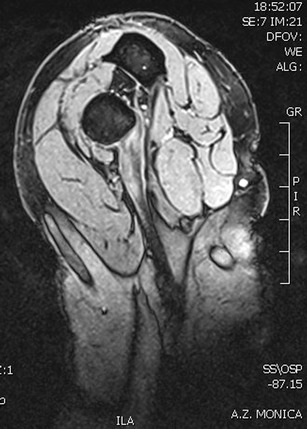

Magnetic resonance imaging [22, 23] (Fig. 4), in particular, the flexion-abduction-supination (FABS) view [24•], can be used for optimal visualization. For the FABS view, the patient is placed prone in the MRI scanner with the affected arm in full abduction above the patient’s head, with the elbow flexed to 90° and the forearm supinated [24•] (Fig. 5). Although an MRI may not be needed to confirm the diagnosis of a complete rupture, the FABS MRI view is especially helpful for the diagnosis and evaluation of partial ruptures and chronic ruptures. It allows for visualization of the entire course of the distal biceps tendon, evaluation for possible partial tear, the formation of scar tissue, and the amount of proximal retraction. This information will help the surgeon prepare for surgery.

Fig. 5.

A FABS view MRI is particularly helpful in partial or chronic tendon ruptures. It allows for a clear view of both the insertion and the course of the tendon. Reprinted with Permission from MoRe Foundation